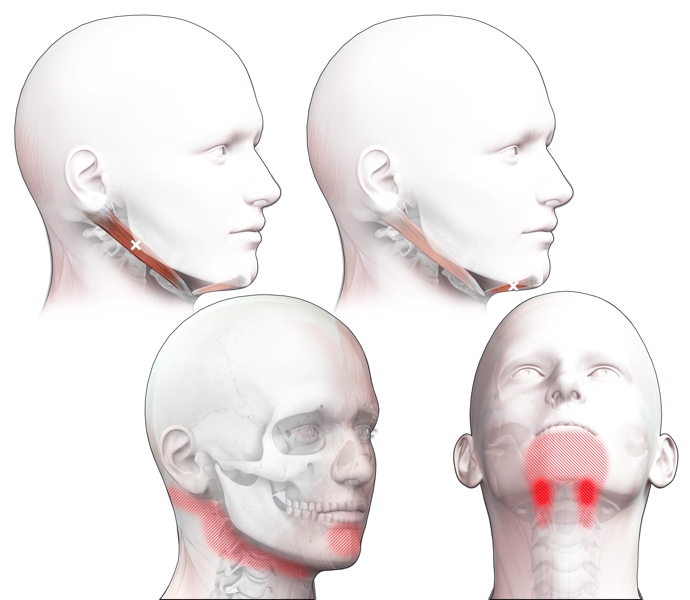

Klachtgebied

Klachten

klachten

Spieren (Nederlands)

Spieren (nederlands)

Spieren (Latijn)

Spieren (latijn)

Trefwoorden

Trefwoorden